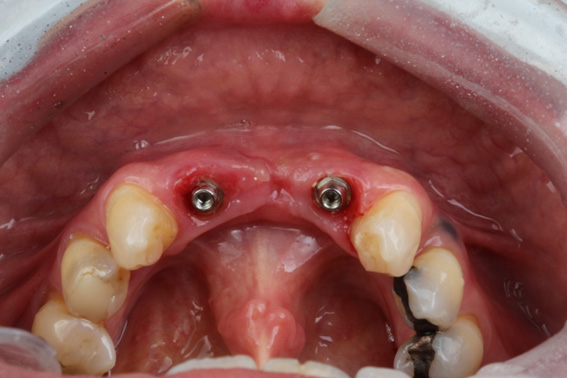

11 | Scan Bodies positioned for scanning